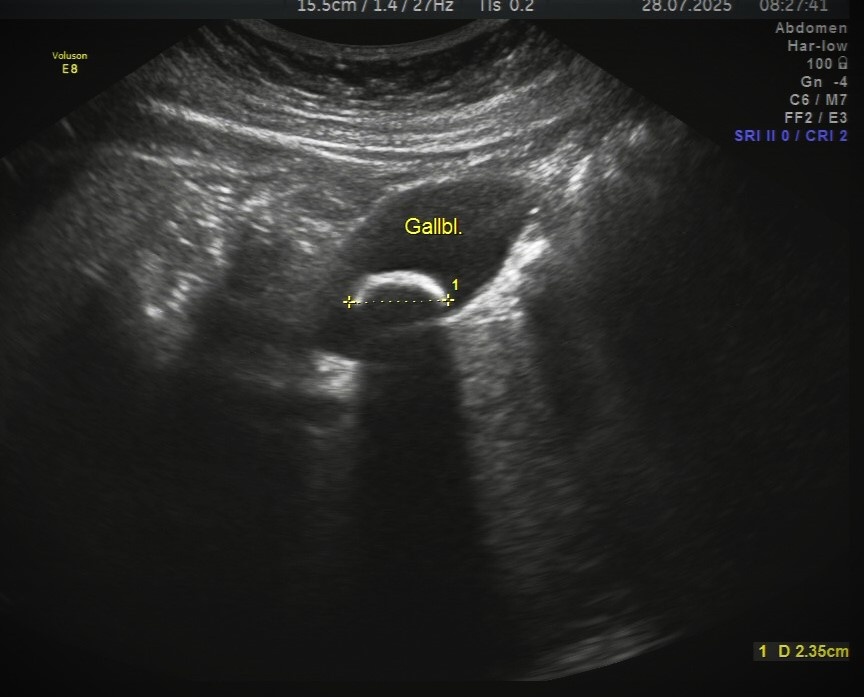

Вот так на УЗи выглядит камень в желчном пузыре (камень выглядит как яркая белая дуга, обозначен желтой пунктирной линией, позади него определяется тень, темная структура вокруг и есть желчный пузырь). До определенного момента желчекаменная болезнь может никак себя не проявлять, чтобы увидеть камень нужно делать УЗИ до появления острых симптомов, особенно в случаях наследственной предрасположенности